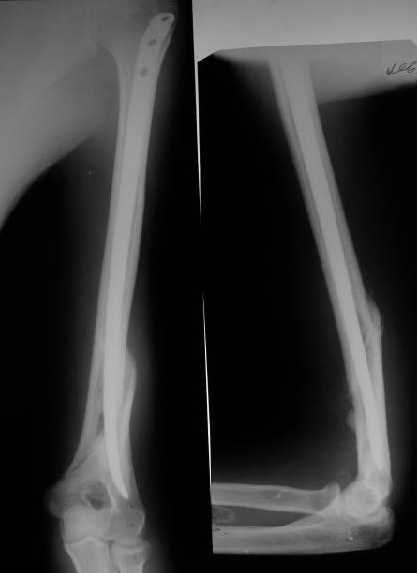

Мы в последние годы все еще используем для переломов такой

локализации эластичные титановые стержни (по мотивам ярославских

разработок, Зверева-Ключевского). Такой стержень можно вводить не

через сухожилие надостной мышцы, а дистальнее.

Снимки до, через 1 и 2 мес. после синтеза.